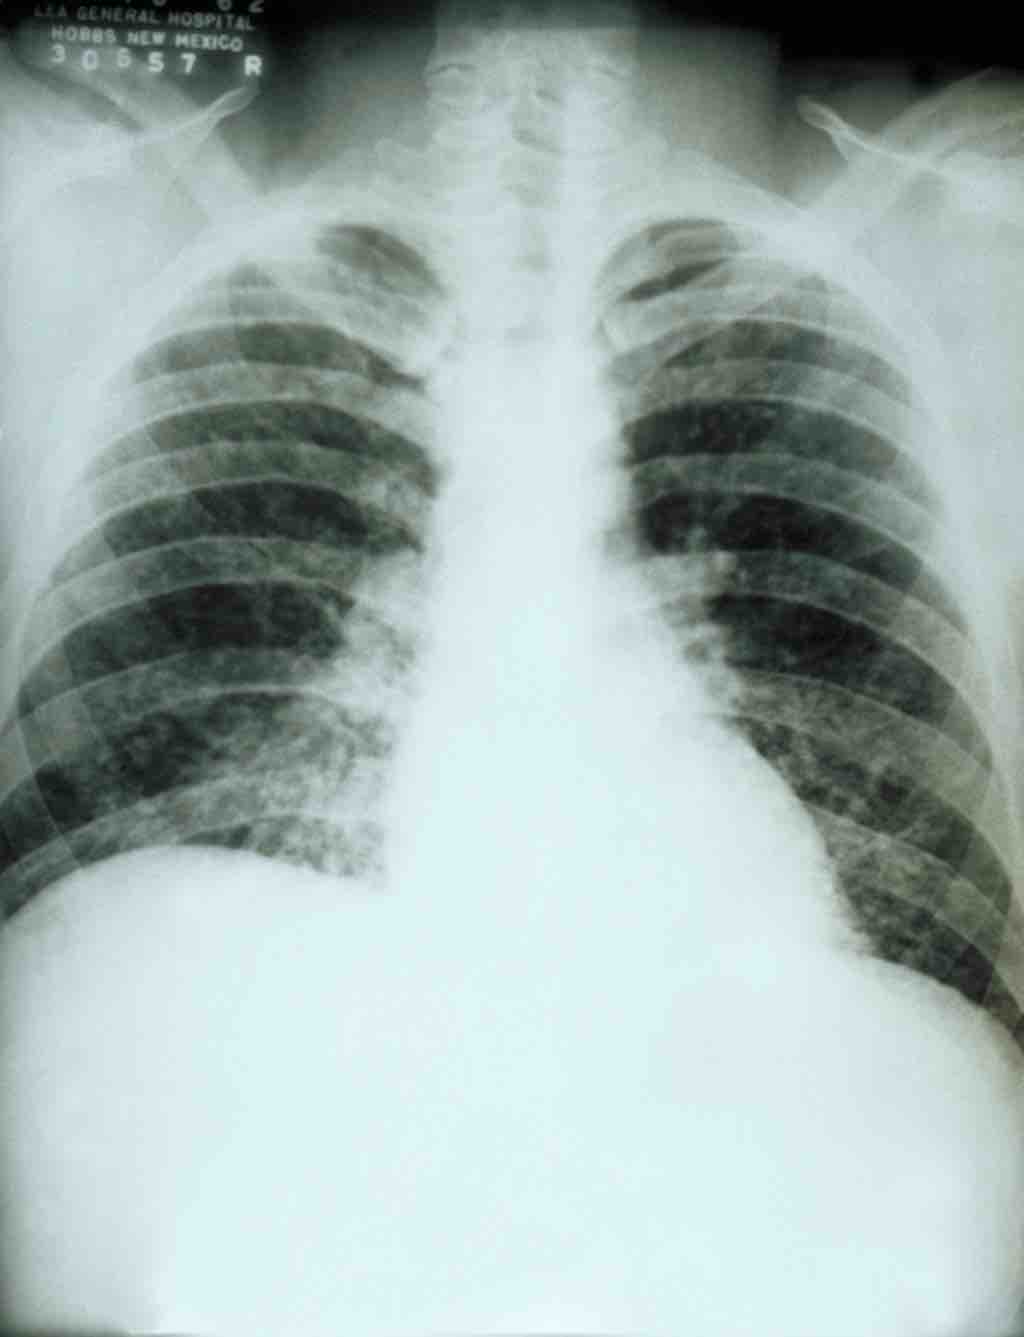

This is a chest X-ray of a patient with acute pulmonary histoplasmosis.